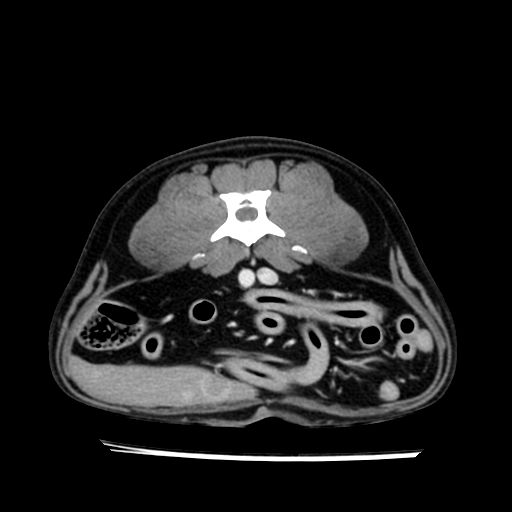

prescritto esame TAC

sequenza immagini limitata al fegato reni e surreni

le immagini ecografiche rispetto alla tac datano circa 7 mesi prima ,le surrenali sono normali nonostante il test acth sia risultato positivo .all’esame TAC dopo diversi mesi risultano aumentate armonicamente nel volume e si individua un forte sospetto di adenoma ipofisario .

sospetto adenoma ipofisario vs. meno probabilmente meningioma della base; intertiziopatia polmonare; lesione espansiva epatica, verosimilmente del lobo laterale sinistro, di sospetta natura neoplastica; lesioni spleniche di natura da definire; iperplasia/ipertrofia delle ghiandole surrenali, bilateralmente; vertebra di transizione del rachide toracico; tenosinovite cronica del muscolo bicipite brachiale di destra.